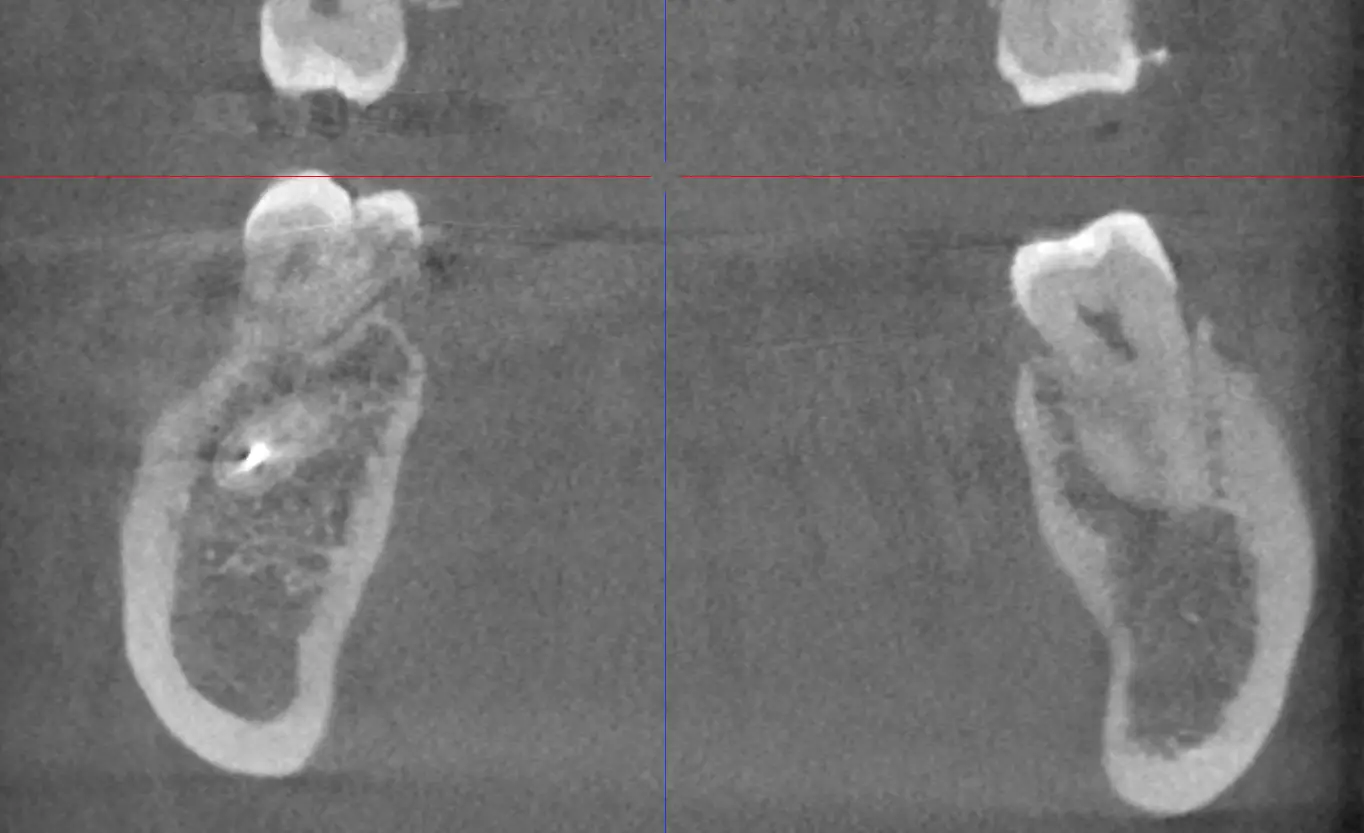

Patient 1_2